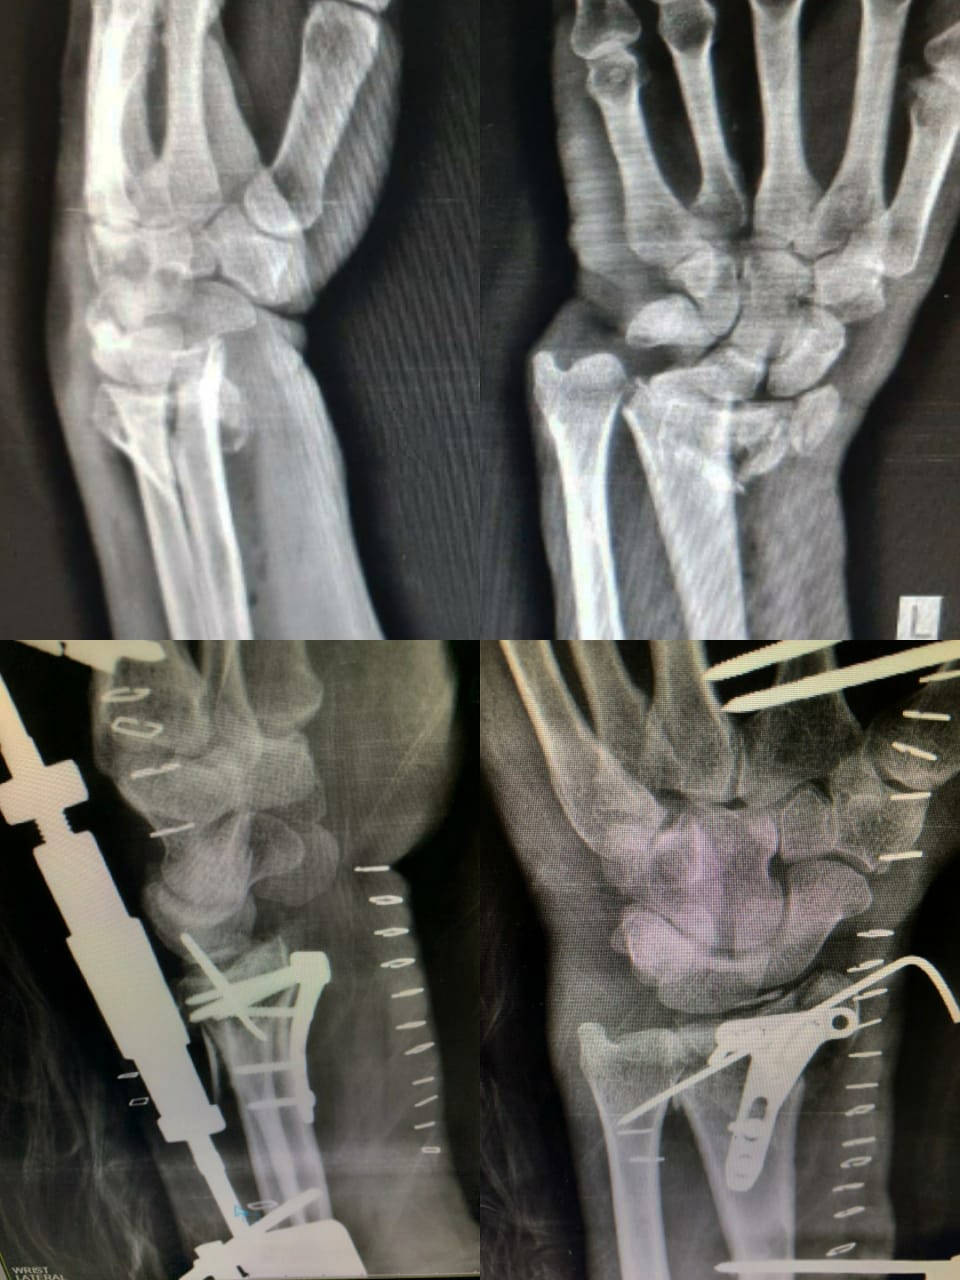

PROFILE TRAINING AND PRESENTATION Dr. Niranjanan Recieving Diploma SICOT degree in Rome, Italy Dr. Niranjanan being awarded fellowship certificate at Indian spinal injuries centre CLIINIC SOME OF Dr. NIRANJANAN's CASES